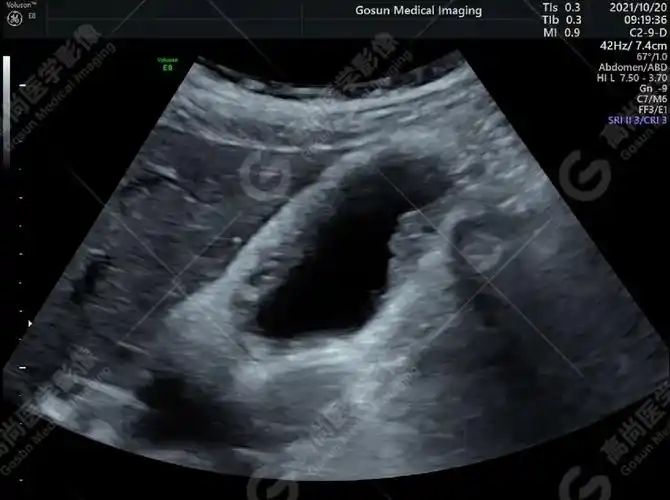

高尚超声:胆囊腺肌症一例